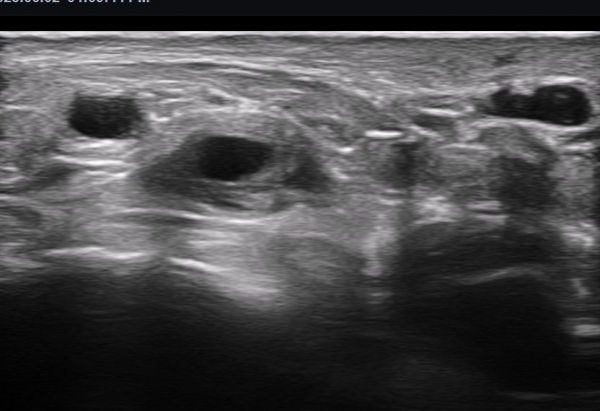

ºñº¹½Å°æ Á¾´Ü¸é°Ë»ç(»çÁø 14, 15)¿¡¼­ ºñº¹½Å°æÀÇ Àü¹ÝÀûÀÎ Àú¿¡ÄÚ ºÎÁ¾°ú ºñº¹½Å°æ ½ÉÃþÀ¸·Î ´Üºñ°ñ°Ç³»

³¶Á¾¼º º¯º¯ÀÌ °üÂûµÈ´Ù.